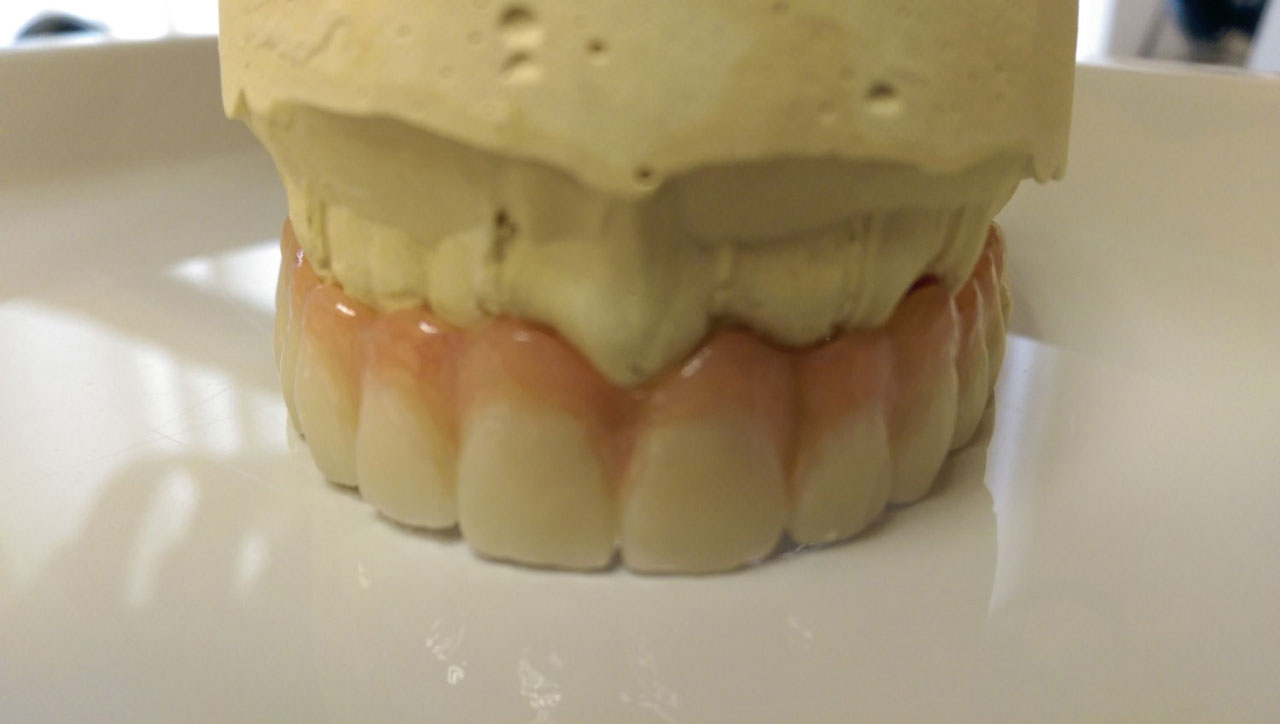

Így néz ki a hosszútávú ideiglenes híd.(Fém vázzal erősített műanyag híd.)

• esettanulmany-11

• esettanulmany-41

Így néz ki a hosszútávú ideiglenes híd. (Fém vázzal erősített műanyag híd.)

• esettanulmany-42